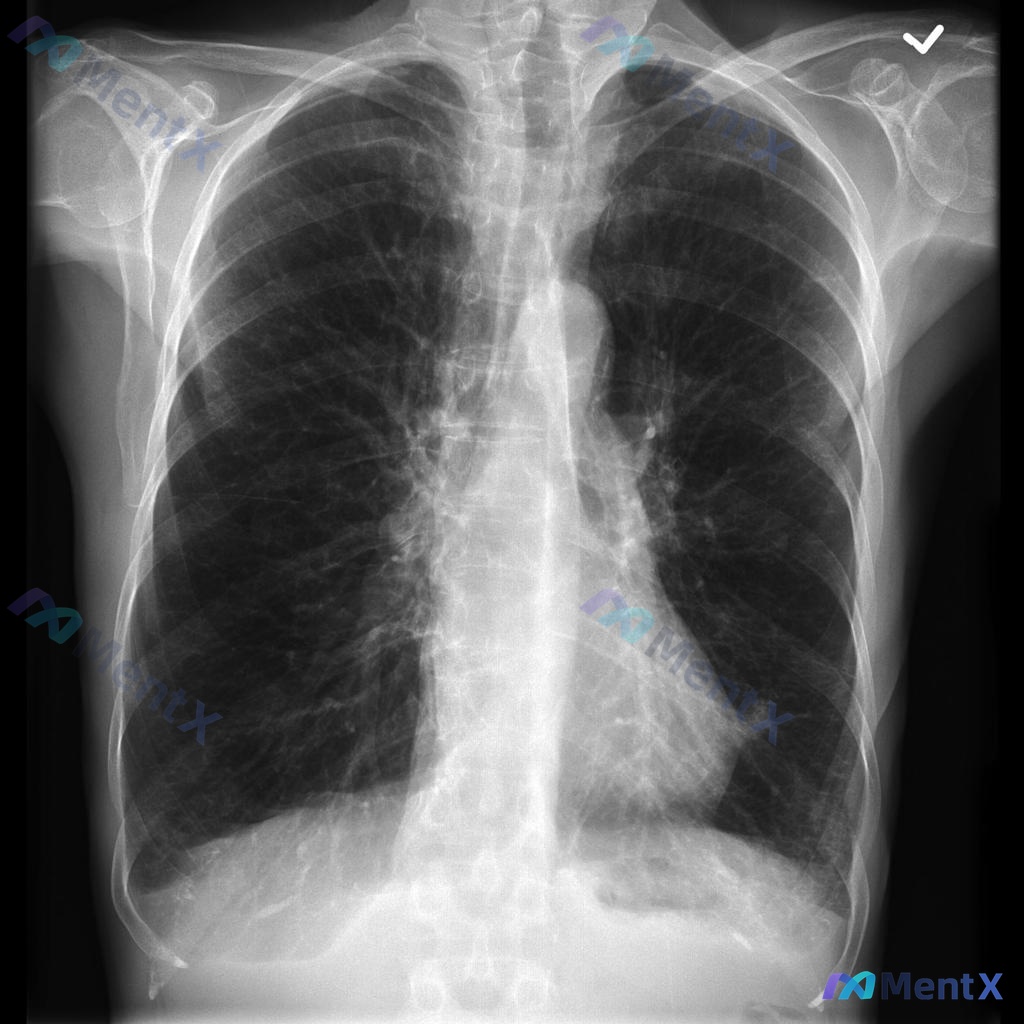

- 胸片(PA位):

- 双肺野透亮度均匀,未见明显渗出、实变、肿块或气胸

- 心影、纵隔、肋膈角均未见明显异常

- 简单说:影像学表现基本正常

这个病例第一眼最突出的是“临床-影像分离”:患者低氧、呼吸窘迫很严重,但胸片几乎“干净”。